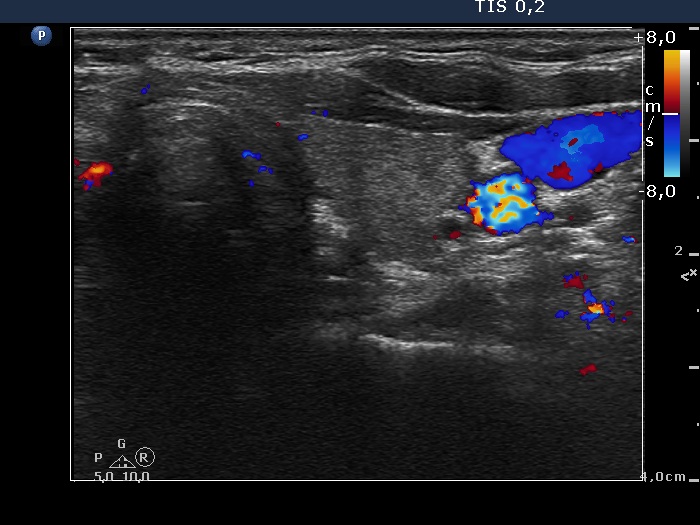

Study on 100 consecutive patients with thyroid nodule - case 006 (ultrasonographic picture 9)

Left lobe, transverse scan, color Doppler mode.